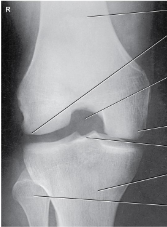

Projection?

AP Lateral Oblique Knee

Patella projected slightly beyond the edge of

the lateral condyle seen on a

AP Oblique Knee

Lateral Rotation

Arthritic knees

Narrowing joint spaces

Varus and Valgus deformities

are seen on a what type of projection

AP Bilateral Weight Bearing